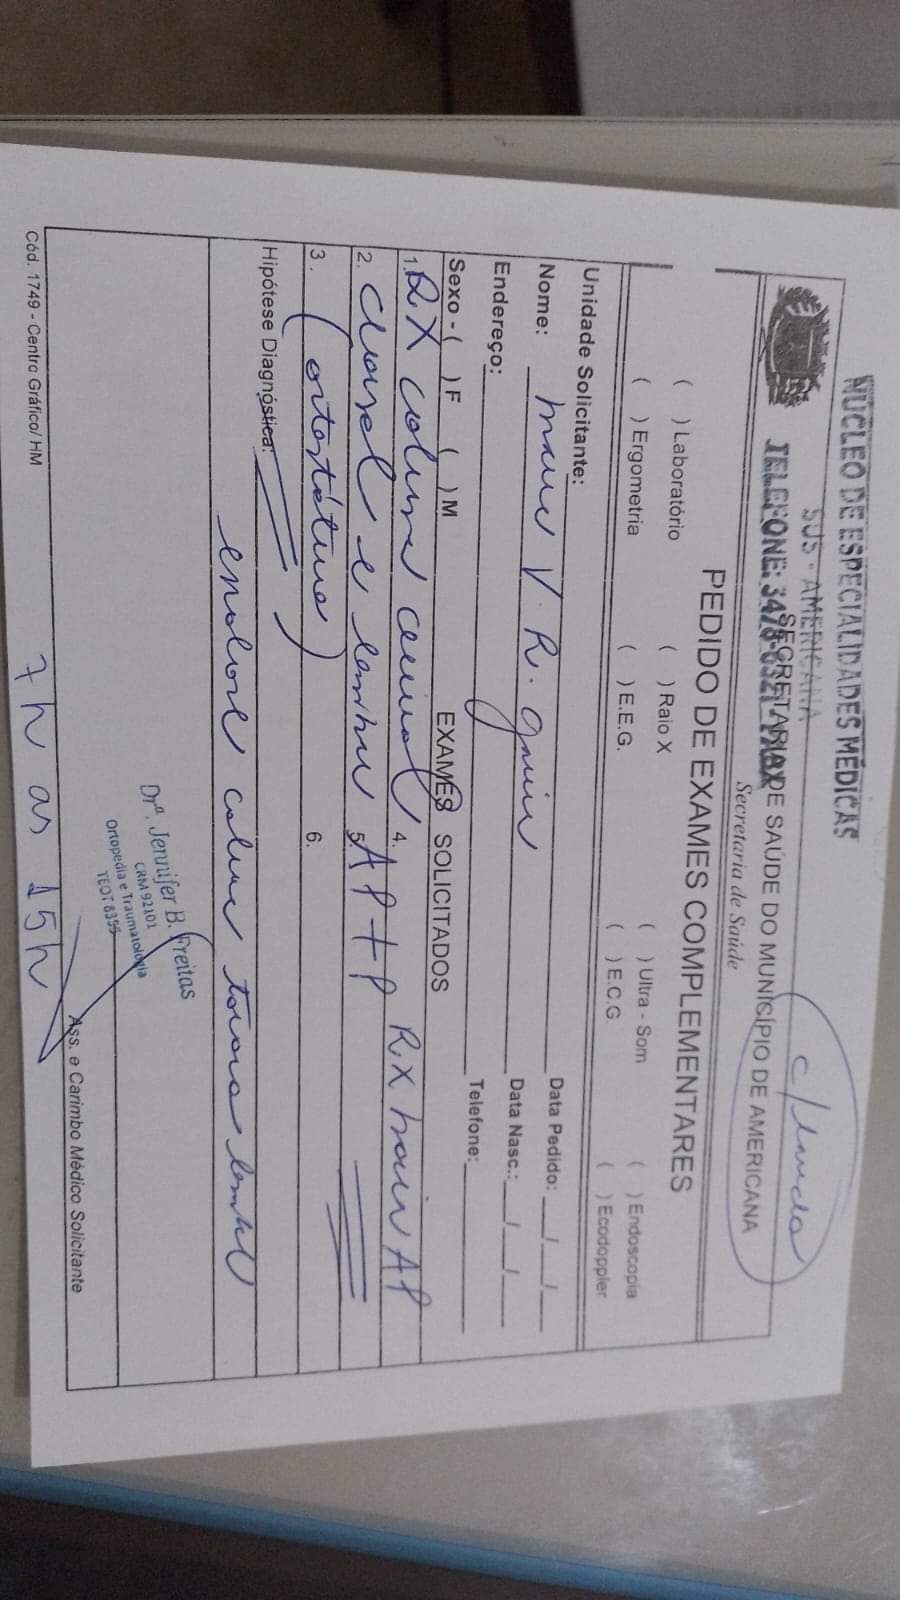

Há um ano mais ou menos descobrimos que tenho escoliose na coluna com uma curvatura mais de 39 graus. Já fiz muitas sessões de fisioterapia recomendada pelo médico, mas de nada adiantou. Minha mãe já fez tudo ao alcance dela, passei no núcleo com a ortopedista Jenifer. Ela me encaminhou para a regional porque está avançado meu caso, e pode prejudicar os meus órgãos, principalmente o pulmão, tenho muita dor, não consigo dormir, os medicamentos que tomo para dor não resolvem e podem me prejudicar futuramente..